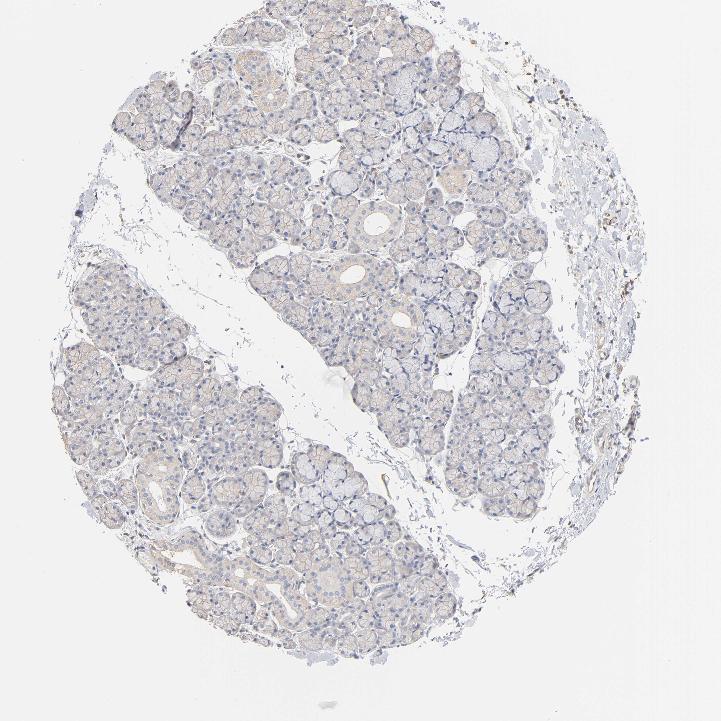

SALIVARY GLAND - Antibody stainingi

Antibody staining in the annotated cell types in the current human tissue is reported as not detected, low, medium, or high, based on conventional immunohistochemistry profiling in selected tissues. This score is based on the combination of the staining intensity and fraction of stained cells.

Each image is clickable and will lead to virtual microscopy that enables deeper exploration of all samples and also displays staining intensity scores, fraction scores and subcellular localization as well as patient and tissue information for each sample.

Antibody HPA003396

Glandular cells Not detected